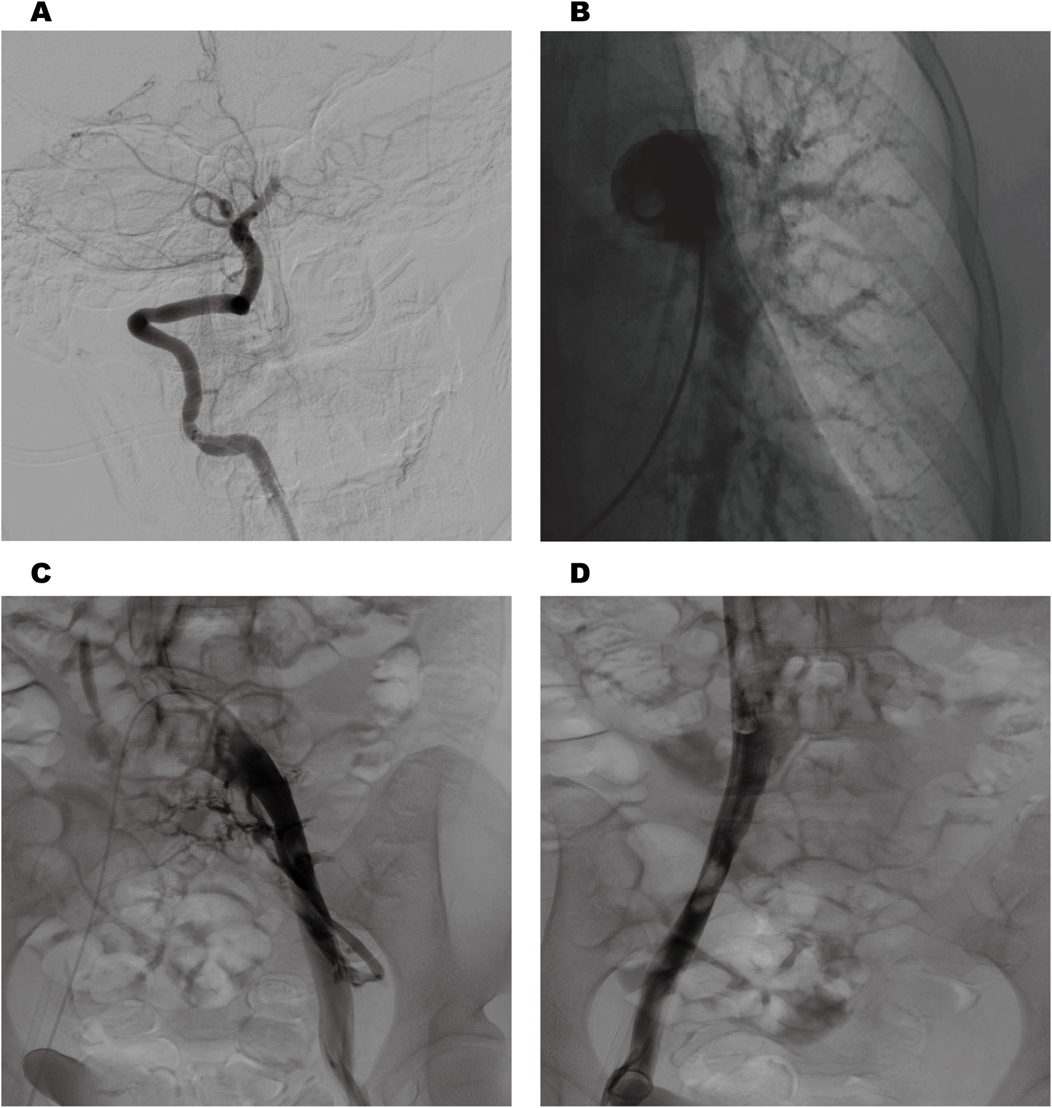

Cranial magnetic resonance imaging (MRI) revealed an acute pontine infarction (Figure 1A). Head and neck computed tomography angiography (CTA) showed basilar artery occlusion (Figure 1B) and incidentally detected left pulmonary artery embolism (Figure 1C), suggesting the possibility of multisystem embolism. Further digital subtraction angiography (DSA) of the whole brain confirmed interruption of blood flow in the distal basilar artery (Figure 2A). Pulmonary angiography revealed left pulmonary artery embolism (Figure 2B). Antegrade venography of the lower extremity deep veins showed bilateral iliac vein thrombosis (Figures 2C,D). The patient underwent emergency mechanical thrombectomy of the basilar artery and placement of an inferior vena cava filter (Figure 3B). Post-operatively, imaging evaluation showed the basilar artery was patent (Figure 3A), and the patient was transferred to the neurology department for further treatment.

Figure 2

Cerebral angiography revealed interruption of blood flow in the distal basilar artery (A) pulmonary angiography revealed left pulmonary artery embolism (B). Antegrade venography of the lower extremity deep veins revealed bilateral iliac vein thrombosis (C,D).